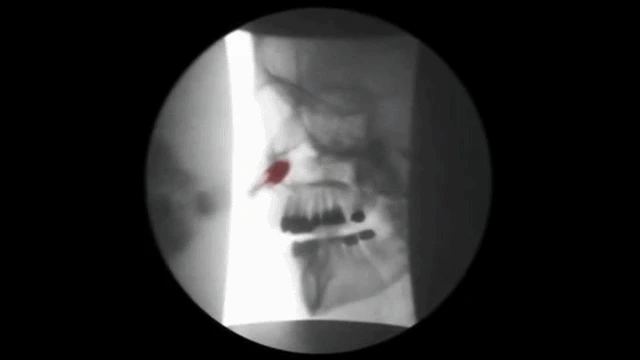

아래의 그림은 휜코로 인한 구조적비염의 치료기법인데

결국 휜코를 치료해야 구조적 비염이 치료되는 것이지요.

치료용 풍선을 코로 넣어 비강과

인두 사이에 위치한 두개 안면 구조물을

확장시켜 고유의 위치로 복구시키는 치료법

그림에서 처럼 풍선을 이용하여 틀어진 비중격을

바로잡고 비중격 교정기를 이용하여 비중격을

바른 위치로 교정하게 됩니다.

이치료는 만성비염환자의 심한 코막힘증에도

탁월한 효과를 나타냅니다.